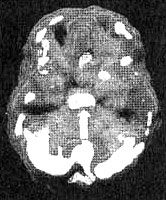

Трехмерное изображение снизу - активный мозг

Эта часть мозга отвечает за эмоциональную настройку организма. Когда активность глубокой лимбической системы понижена, мы пребываем, как правило, в позитивном, более оптимистичном расположении духа. Если же эта область "перегрета" или гиперактивна, эмоциональное состояние человека ухудшается. Поначалу это открытие удивило и меня, и моих коллег в нашей клинике. Мы подумали, что повышенная активность в той части мозга, которая отвечает за эмоции, может соответствовать усилению чувств по всей длине спектра, а не только негативных. Тем не менее вновь и вновь мы убеждались в том, что, когда на снимках SPECT эта область оказывалась гиперактивной, это было связано именно с депрессией и отрицательными эмоциями у нашего пациента. Похоже, что воспаление в глубокой лимбической системе приводит к появлению болезненной эмоциональности. Это подтверждается и новыми результатами изучения депрессии в других лабораториях во всем мире.